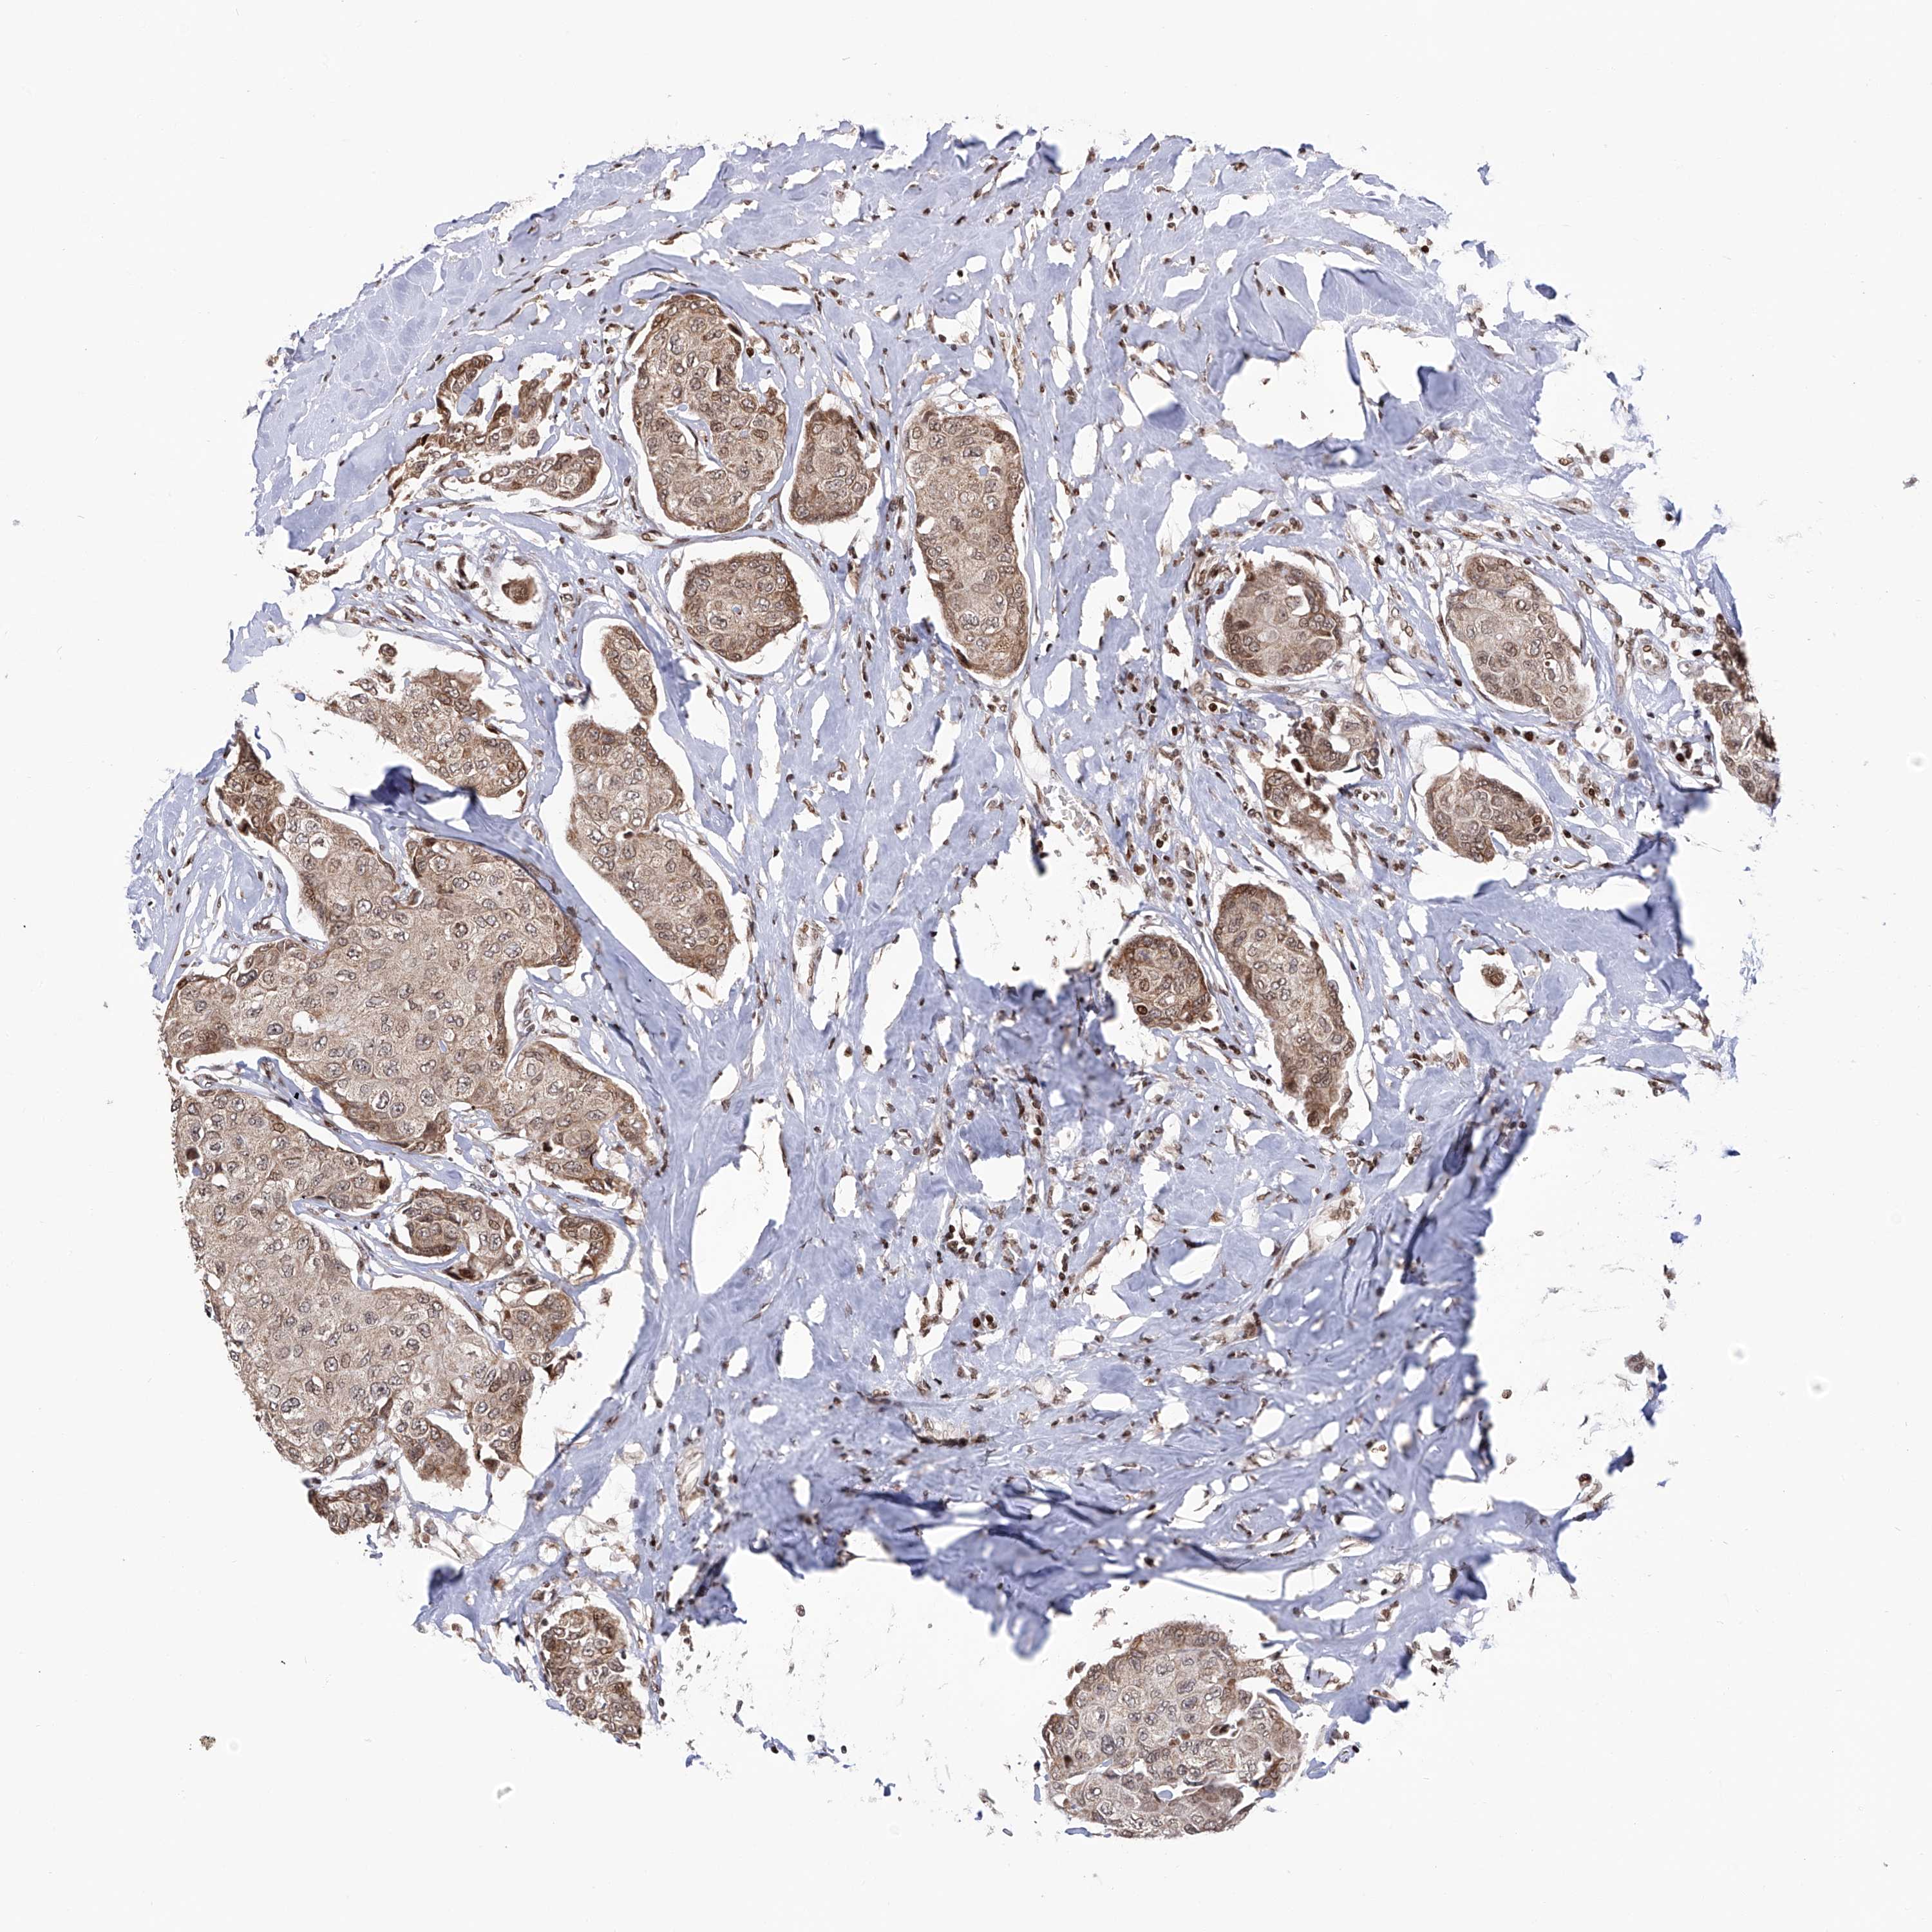

CANCER BREAST CANCER Show tissue menu

Breast cancer

Human cancer